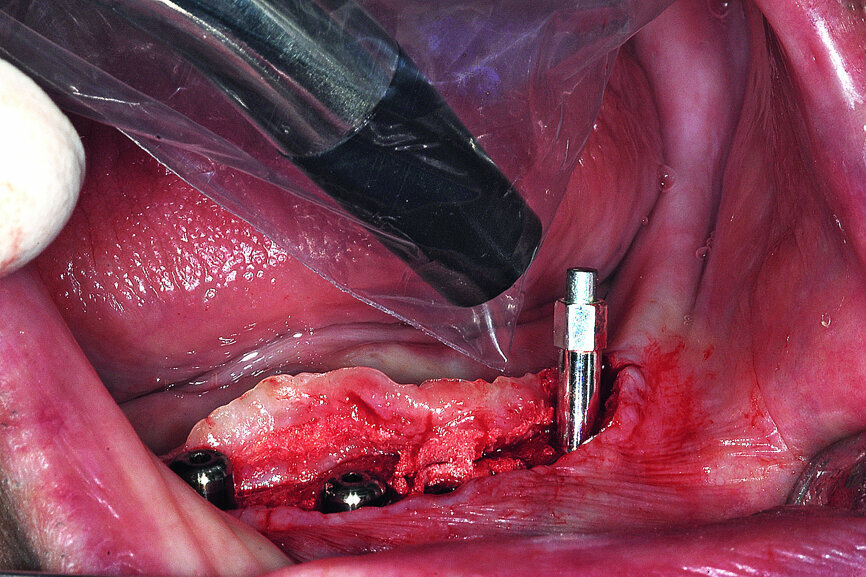

Fig. 17: Each of the four implants was measured for implant stability with the implant specific SmartPeg.

Each implant was tested by resonance frequency analysis (RFA) to document implant stability with an implant-specific SmartPeg to record an implant stability quotient (ISQ) value (IDx Osstell). Clinicians might consider the importance of assessing implant stability for every implant placed using a non-destructive and objective protocol well-documented in the scientific literature. Additionally, significant and differing entirely from insertion torque values is that ISQ values can be monitored over time which is especially important when a two-stage surgical approach is anticipated as in this case example.

After the site was allowed to mature for three months, a midline incision carefully split the narrow band of keratinised tissue to uncover the grafted site and the underlying four implants, which were all covered with a small layer of immature bone. Once fully exposed, each implant was once again fitted with a SmartPeg to assess an ISQ value, which was then compared with the initial values to determine the progress of osseointegration and to confirm implant stability (Figs. 19a & b). The ability to measure stability over time provides invaluable information for the clinician about the health of each implant. A favourable ISQ value imparts a level of confidence and knowledge of when an implant can be loaded and restored. Healing collars were positioned to allow for the soft tissue to be approximated and sutured.

At the time of implant placement, the RFA/ISQ values were recorded. The initial values were actually acceptable if immediate loading was desired (over 70), based upon the excellent stability afforded by the thread design of the implant engaging the buccal and lingual cortex, and apical length into native bone. A two-stage approach was elected due to the large hollow areas in the symphysis, which were grafted and covered with PRF. At three months, the implants were found to be covered with a thin layer of immature bone, and the intramedullary area seemed solid. The second series of measurements were recorded to reflect the status of integration. All values increased significantly, verifying that the process of osseointegration was progressing positively, and loading was appropriate. Overdenture abutments (Meg-Rhein) were secured to each implant, and stainless-steel housings with retentive caps were embedded into the denture.